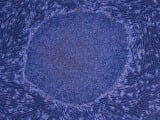

ヒトiPS細胞(human iPS)撮影:京都大学iPS細胞研究所 (2/2枚)

• ノーベル医学生理学賞受賞が決まった京都大学の山中伸弥教授 ヒトiPS細胞(human iPS)撮影:京都大学iPS細胞研究所